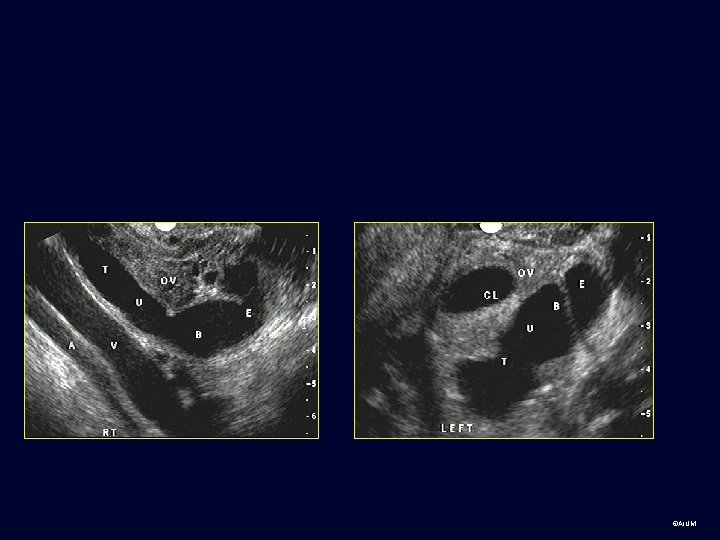

Ovary • The ovaries are ellipsoid and can be identified in menstruating females by the presence of follicles. ©AIUM

Practice cases for students: Normal and abnormal • Transabdominal, transvaginal or can’t tell? • Body part? • Normal or abnormal (provide diagnosis or Ddx if possible) ©AIUM

Group 1 ©AIUM